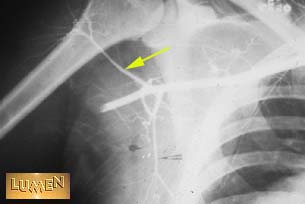

35. Identify.

Answer

Posterior humeral circumflex a.